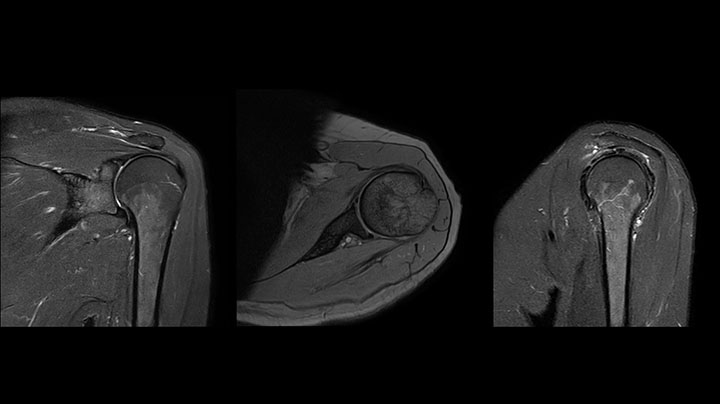

The Prodiva shoulder coil is very flexible and has large coverage, which makes good positioning easier, and that contributes to the superb image quality and high SNR that we get in our shoulder exams.

Scan time 2:55 min, FOV 160 mm, acq voxels 0.55 x 0.83 x 3.0 mm.

Scan time 4:19 min, FOV 160 mm, acq voxels 0.55 x 0.80 x 3.0 mm.

Scan time 2:50 min, FOV 160 mm, acq voxels 0.70 x 0.99 x 3.0 mm.